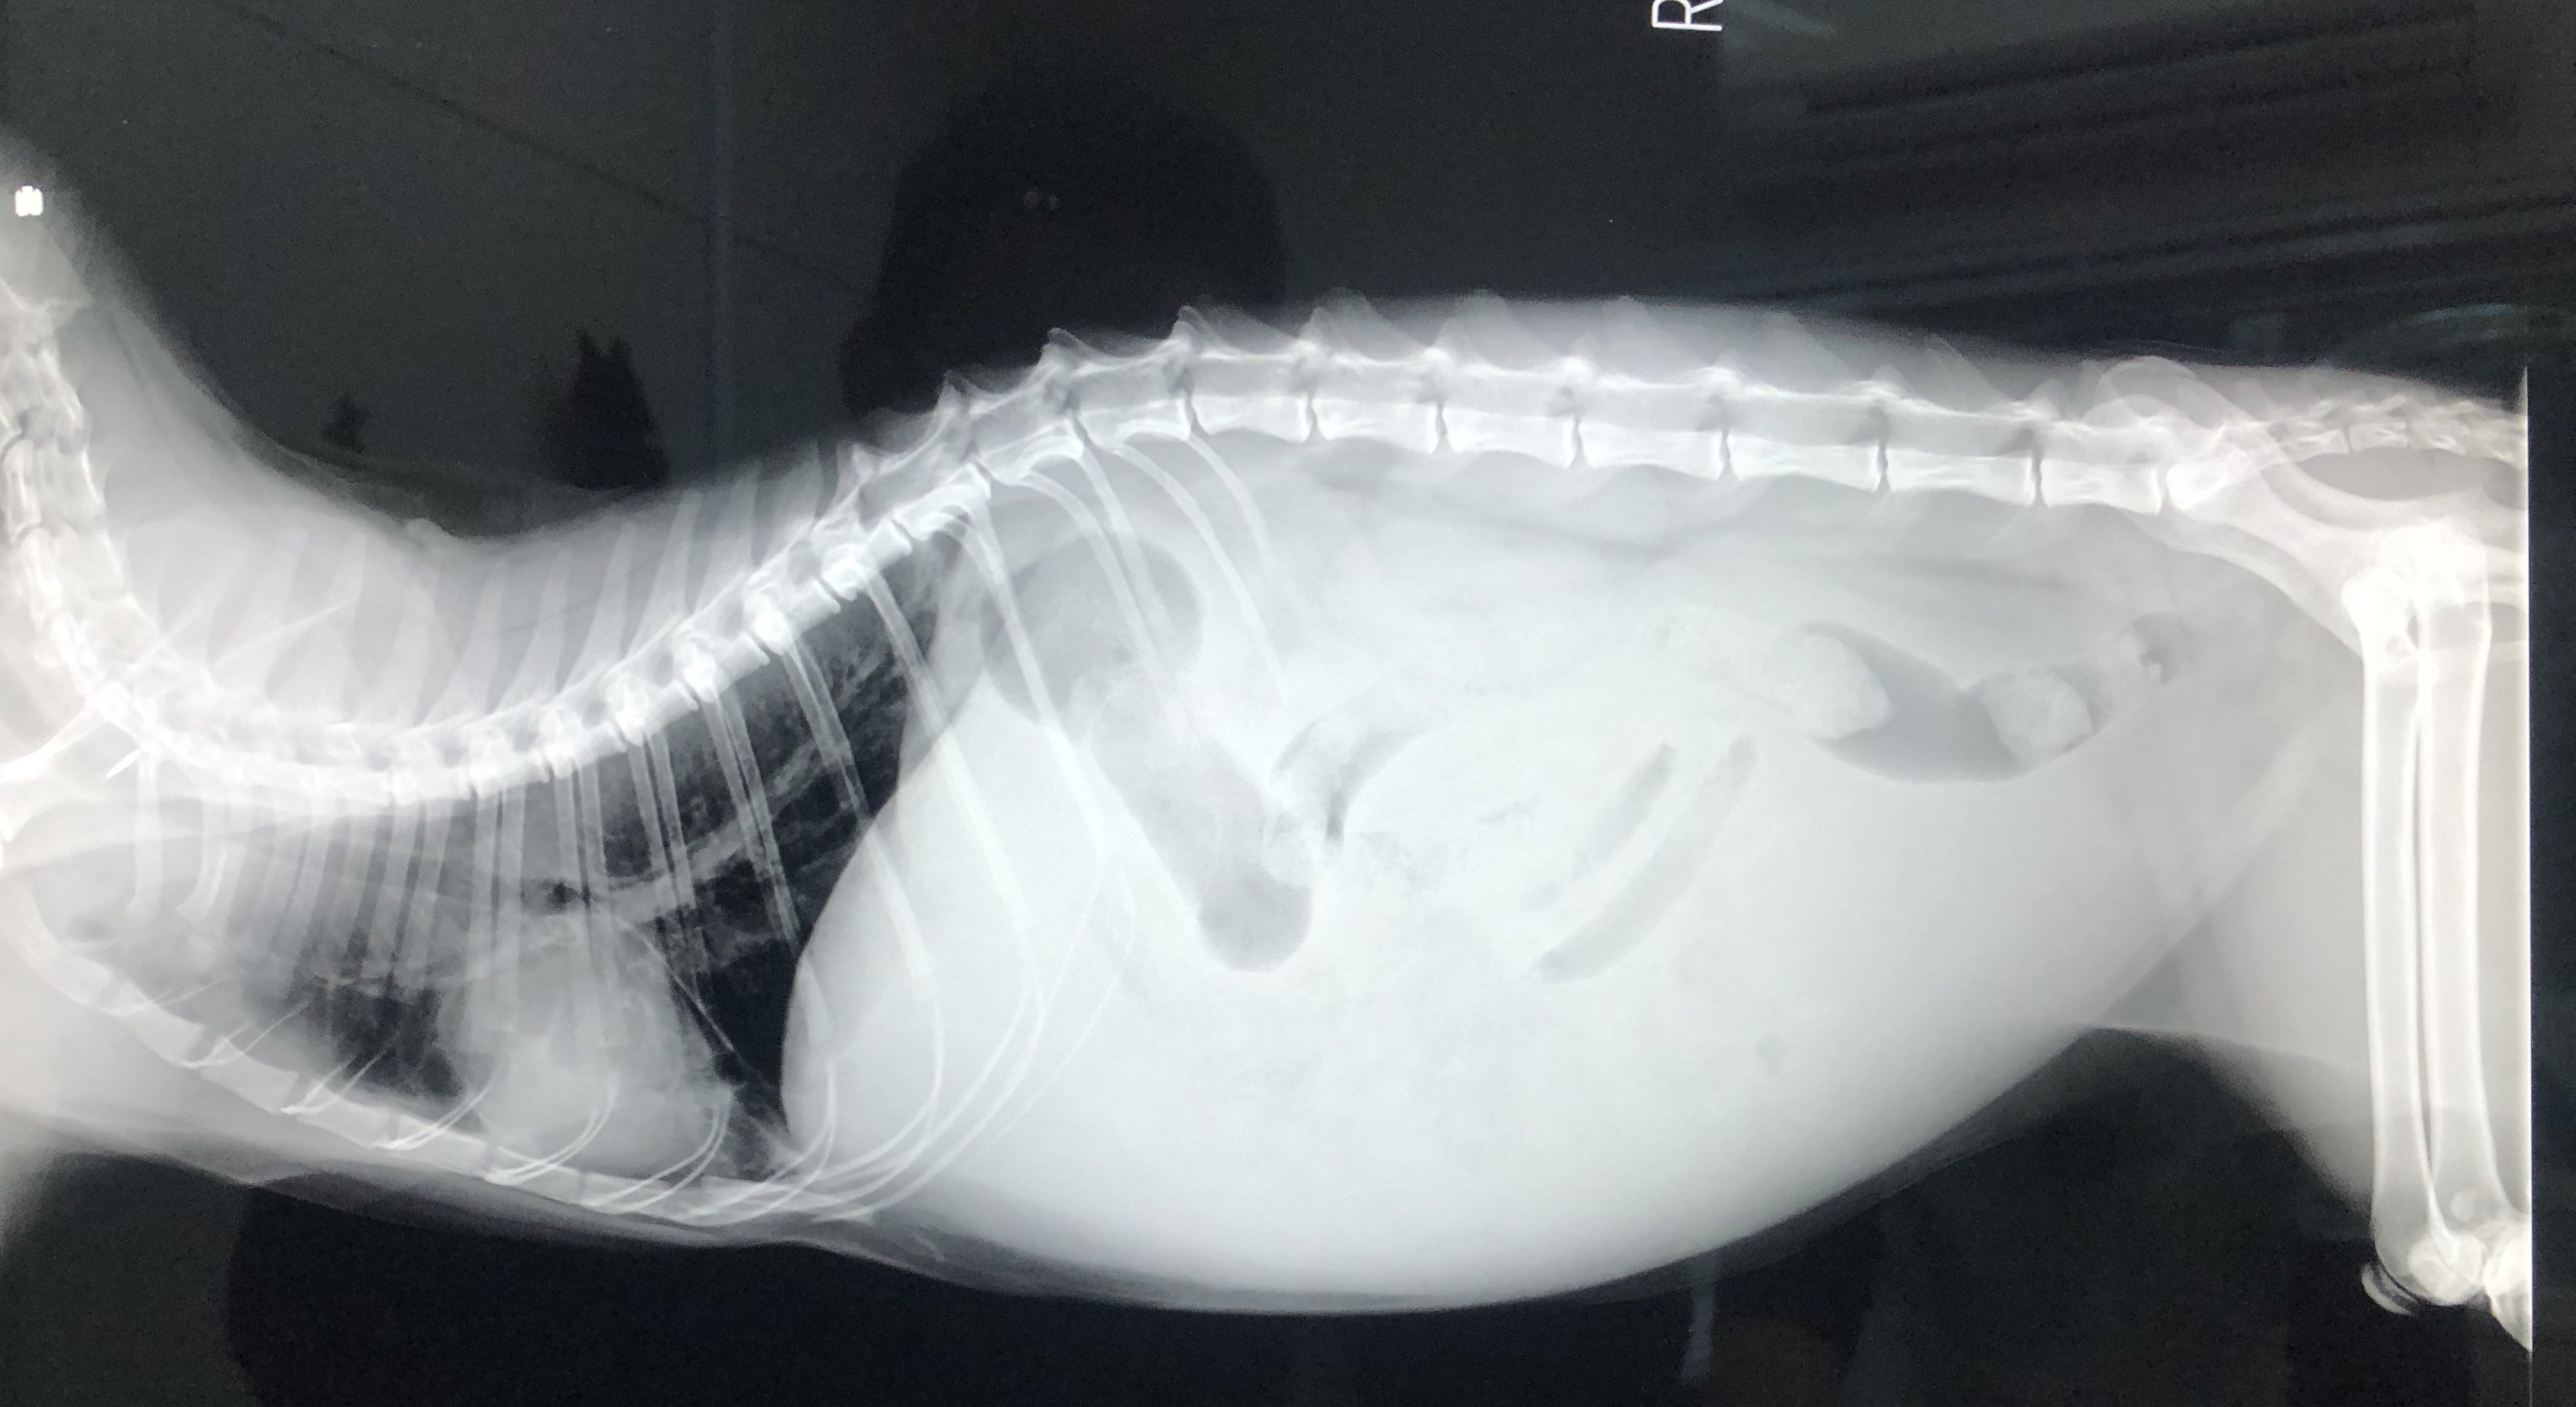

FIPという診断を受けた時に、あらゆる手段を使いこの病気について調べました。動物病院の先生やネットで調べた結果、外猫・野良猫のほとんどが持っているコロナウイルスが突然体内で変異し、FIPウイルスになるということが分かりました。FIPウイルスは一度発症してしまうと元に戻ることはありません。原因はストレスのことが多いと言われており、ずら丸にストレスを与えてしまっていたと日々嘆くばかりです。現在の症状としては腹水・胸水の貯留、食欲減退、便秘、黄疸、脱水症状です。動物病院への通院で脱水症状については収まりを見せていますが、その他は改善の兆しが見えてきません。

ずら丸の腹水が溜まっているのを見た際、リンパ癌や心臓の病気など様々な病気を疑いました。しかし考えていたよりも状況は重く、不治の病と言われるFIPでした。世界中にFIPで苦しんでいる猫、オーナー様はいらっしゃいます。MUTIANの治療で完治し、1つの道しるべとすることが出来れば、FIPの診断で悲しむ方は減るのではないかと思います。